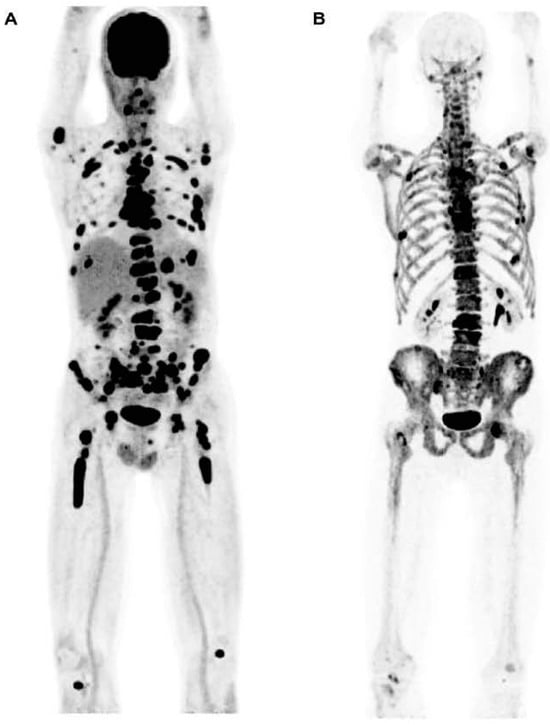

Fractures, which impact 60–80% of myeloma patients, represent a notable adverse consequence of myeloma bone disease. While [18F]FDG can reveal fractures to a certain degree, numerous studies have demonstrated that a bone-seeking PET radiotracer, 18F-sodium fluoride (Na[18F]F), is more effective for this specific purpose [38] (Figure 7). On the other hand, most comparative studies showed that [18F]FDG is superior to Na[18F]F in identifying osteolytic lesions [38] (Figure 3). This outcome is anticipated due to the fact that Na[18F]F reflects osteoblastic activity, whereas localized myeloma lesions predominantly involve heightened osteoclast activity [38].

Figure 7.

(A) This image displays the whole-body Na[18F]F PET scan without the application of regions of interest (ROIs). (B) Active lesions including fractures throughout the whole-body Na[18F]F PET/CT scans were identified and segmented; PMID: 32929393, Figure 1, open access.

In a research conducted by Ak et al. [39], even though there were certain limitations to the ability of Na[18F]F PET to identify osteolytic lesions, this radiotracer managed to identify 135 bone lesions, encompassing rib fractures and other anomalies linked to degenerative alterations. Hence, the researchers concluded that Na[18F]F PET/CT might offer a complementary function in identifying fractures linked to myeloma [39]. In another study conducted by Sachpekidis et al., the Na[18F]F PET/CT scan revealed only 135 lesions indicative of MM, whereas the whole-body [18F]FDG PET/CT scan depicted a total of 343 focal lesions [40]. Nonetheless, Na[18F]F PET/CT revealed indications of degenerative processes associated with trauma [40].

8. PET for Assessment of Bone Turnover in Myeloma Patients

The presence of fluoride in Na[18F]F serves as a direct marker of osteoblastic activity, as it is specifically incorporated into newly formed bone mineral sites that are exposed [41]. Consequently, Na[18F]F PET can be utilized to evaluate bone turnover in different medical conditions. Zirakchian Zadeh et al. investigated the effects of high-dose therapy (HDT) and conventional-dose chemotherapy on the uptake of Na[18F]F in myeloma patients [42]. In total, 19 patients with MM who received HDT and an additional 11 MM patients who received chemotherapy at standard doses were included in the study (Figure 8) [42]. Following HDT, myeloma patients exhibited a noticeable decrease in Na[18F]F uptake in various areas, including the overall skeleton, pelvis, entire femoral neck, and lateral femoral neck. Conversely, in the non-HDT group, no significant alterations were observed (Figure 8) [42]. As a result, the authors inferred that Na[18F]F holds potential for evaluating bone loss in myeloma patients after HDT [42].

Figure 8.

The images on the left depict a semi-automated CT-based segmentation used to assess bone turnover in the entire bone and pelvis of multiple myeloma patients before and after treatment (a,b). Regions of interest were also delineated to evaluate changes in Na[18F]F uptake in the femoral neck of these patients (c). Images obtained from comparison of Na[18F]F uptake in the whole bone, pelvis, and femoral neck of multiple myeloma patients before and after high-dose therapy and conventional-dose chemotherapy, Zirakchian Zadeh et al., EJNMMI, Figures 2 and 5, obtained with permission; reference [42] in this review article.